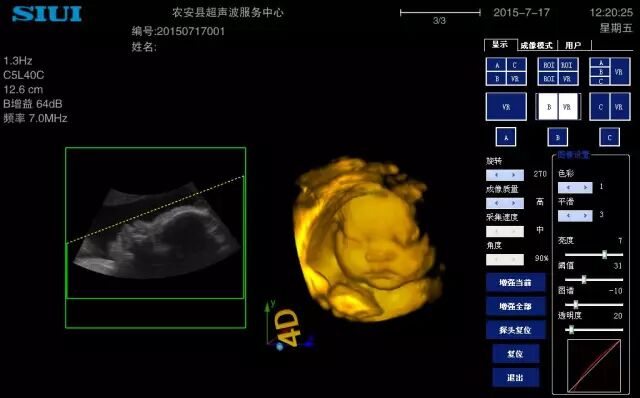

46、做胎儿三维时,胎儿的面部和孕妇的子宫壁贴的太近,就无法取得好的图像,让其他人用双手轻轻挤压胎儿颜面双侧的宫壁,让胎儿的脸与宫壁间有较足够多的羊水空间,面部的三维图像就漂亮了。